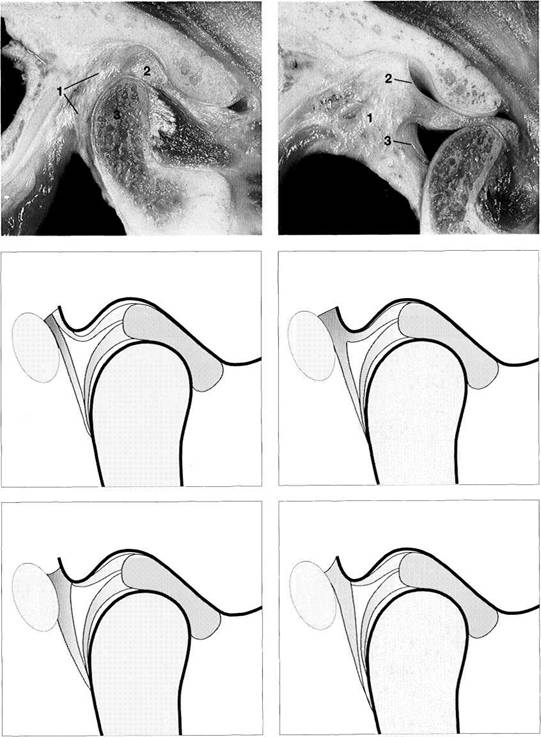

Fourteenth week

Sagittal section of a human disk-condyle complex. A distinct joint space has now formed between the condyle (1) and the disk (2). Above the disk the temporal blastema begins to split away to form the upper joint space (arrows). The cartilage of the condyle is increasingly replaced by bone from below. However, remnants of the original cartilage remain in the neck of the condyle until past puberty.

Sixteenth week

Horizontal section of a human temporomandibular joint during the sixteenth week of embryonic development. Insertion of the lateral pterygoid muscle (1) onto the condyle (2) can be clearly identified. In agreement with reports in the literature (Ogutcen-Toller and Juniper 1994, Ogutcen-Toller 1995), the discomaleolar ligament (arrows) runs from the joint capsule through the tympanosquamosal fissure to the malleus (3) as an extension of the muscle.

Eighteenth week

Frontal section through a human temporomandibular joint in the eighteenth week of embryonic development. The fossa (1), disk (2) and condyle (3) are completely developed and from now on will experience only an increase in size. The joint capsule (arrows) can also be clearly identified. The cartilaginous condyle will ossify further. Distribution of cartilage at this stage indicates that future growth will be primarily in the laterosuperior direction.

Contributed by R. Wurgaft Dreiman